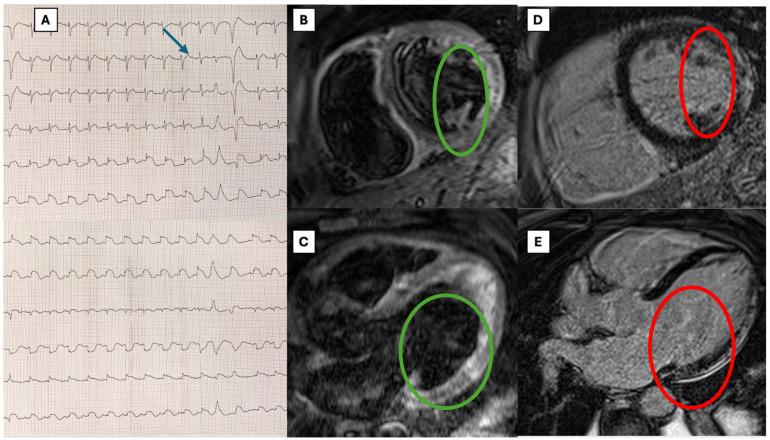

Toxic myocarditis (TM) is rare, and no systematic evidence is available regarding its treatment or prognosis. Hydrocarbons even more rarely cause TM, and they are associated with severe extracardiac toxicity. Moreover, a pathogenic interaction between viral and toxic agents in TM has not been studied. We present the first case of biopsy-proven parvovirus B19 (B19V) viral fulminant myocarditis diagnosed after hydrocarbon exposure, along with a systematic literature review of hydrocarbon-TM cases. A systematic literature review was conducted by searching hydrocarbon-TM cases. Clinical and prognostic data were recorded. After screening of 937 records, 7 were included. All cases were male, with a median age of 24 years (IQR 23-25). Chest pain and dyspnea were the main symptoms, but arrhythmic presentation was also reported; endomyocardial biopsy (EMB) was performed in only one case. Overall, treatment was based on supportive measures, such as antiarrhythmic and/or vasoactive therapy. Our example (male, 47 years old) is the first reported fulminant biopsy-proven case diagnosed after a massive exposure to hydrocarbons, in which EMB molecular analysis unexpectedly revealed B19V with a high viral load. Hemodynamic and arrhythmic instability required percutaneous stellate ganglion blockade and temporary wearable defibrillator use. Left ventricular function spontaneously normalized at 3 months. In conclusion, we report the first fulminant B19V myocarditis case temporally associated with aromatic hydrocarbon exposure due to a coexistence of viral and toxic causes. Our case and the systematic review show that promptly performing EMB can provide a definitive diagnosis and guide treatment, especially in severe cases in which infectious agents may contribute to myocardial damage.

中毒性心肌炎(TM)较为罕见,目前尚无关于其治疗或预后的系统性证据。碳氢化合物引发TM的情况更为罕见,且与严重的心外毒性相关。此外,TM中病毒与毒性因子之间的致病相互作用尚未得到研究。我们报告了首例经活检证实的细小病毒B19(B19V)暴发性心肌炎病例,该病例在接触碳氢化合物后被诊断出来,并对碳氢化合物相关TM病例进行了系统性文献综述。通过检索碳氢化合物相关TM病例进行了系统性文献综述。记录了临床和预后数据。在筛选937条记录后,纳入了7例。所有病例均为男性,中位年龄24岁(四分位间距23 - 25岁)。胸痛和呼吸困难是主要症状,但也有心律失常的表现;仅1例进行了心内膜活检(EMB)。总体而言,治疗基于支持性措施,如抗心律失常和/或血管活性治疗。我们的病例(47岁男性)是首例报道的在大量接触碳氢化合物后经活检证实的暴发性病例,其中EMB分子分析意外发现高病毒载量的B19V。血流动力学和心律失常不稳定需要进行经皮星状神经节阻滞并使用临时可穿戴式除颤器。左心室功能在3个月时自发恢复正常。总之,我们报告了首例因病毒和毒性因素共存而在时间上与芳香烃暴露相关的暴发性B19V心肌炎病例。我们的病例和系统性综述表明,及时进行EMB可提供明确诊断并指导治疗,尤其是在感染因子可能导致心肌损伤的严重病例中。